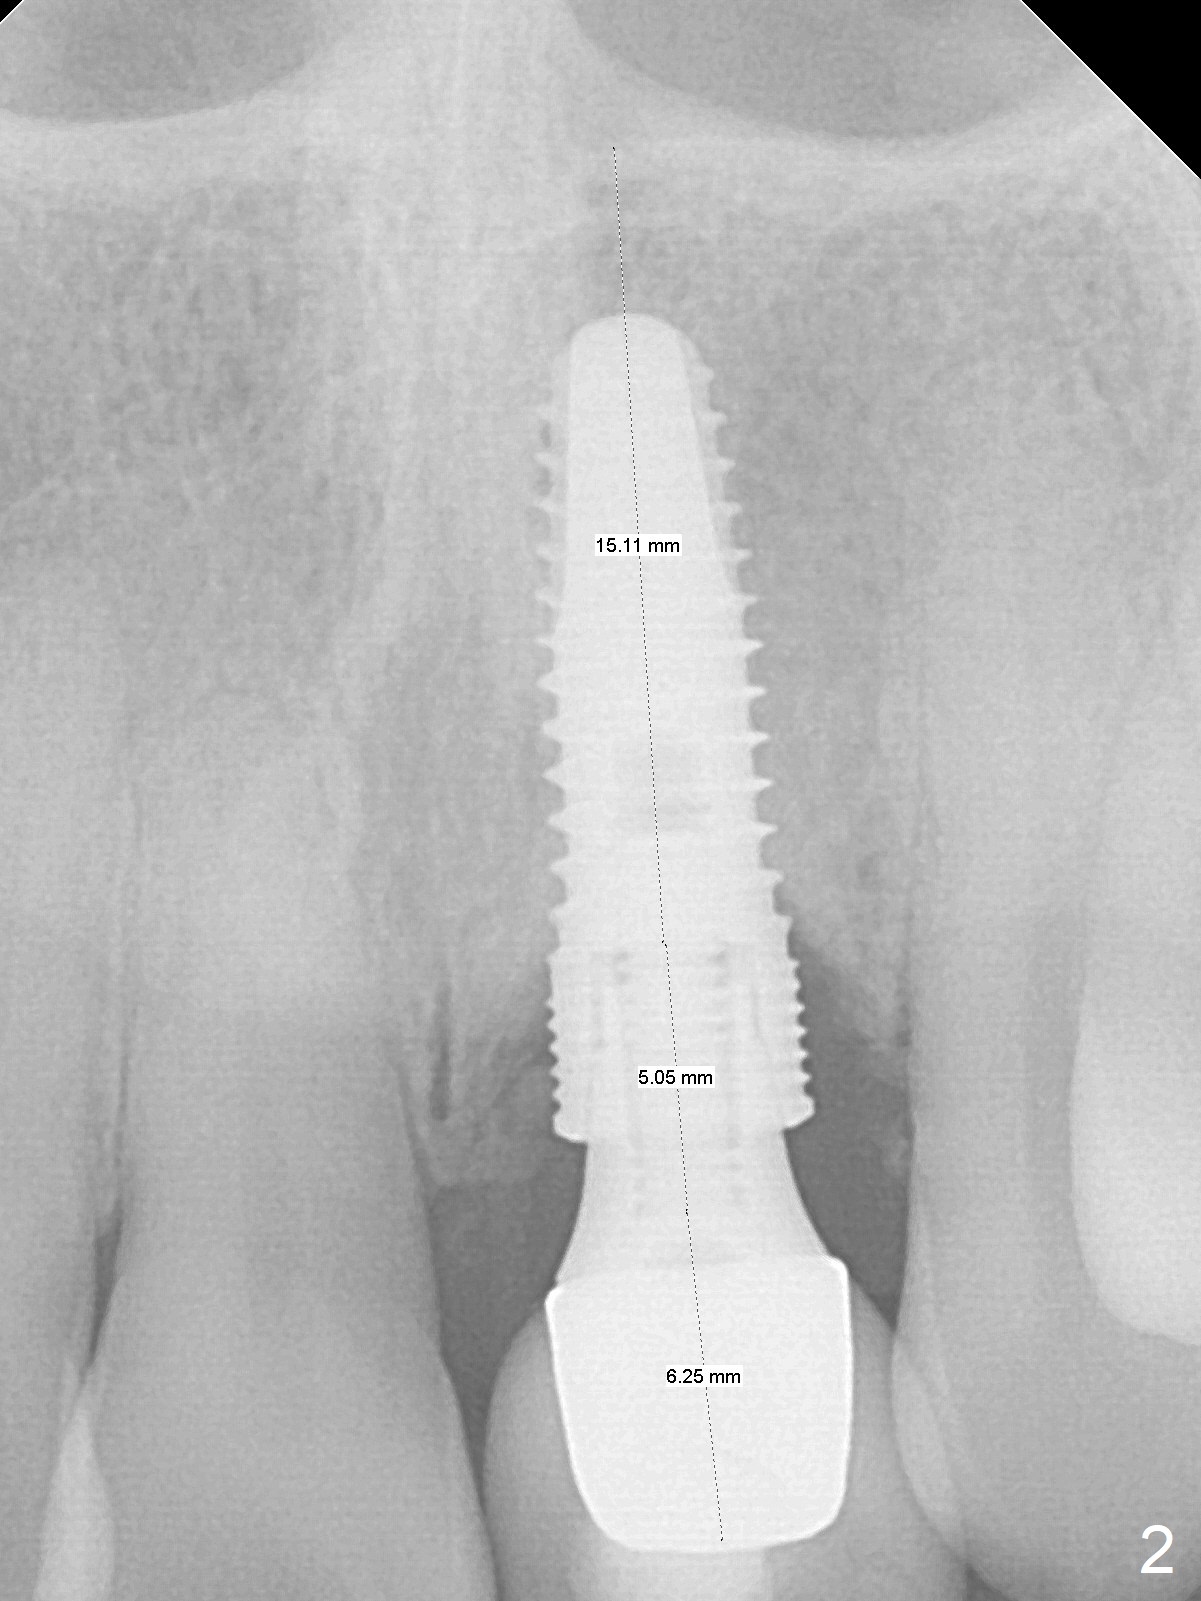

A 56-year-old woman finally agrees to redo the implant (4.5x14 mm) with repeated screw loosening and periimplantitis (chief complaint "gum bleeding while using Water Pik", Fig.1).  To reduce the 1st complication, a 1-piece implant will be chosen.  To decrease the 2nd one (i.e., to place the implant deep), an abutment with 4 mm cuff will be used.  To achieve primary stability, initiate osteotomy in the apical bone ~ 3 mm.  Autoclave 2 endo stoppers and use the longest 1.5 mm drill or one from 1-piece kit with a drill extension.  After implant removal (Metronidazole), measure the osteotomy depth using drill stopper and probably the soft tissue landmark and drill for 3 mm.  If the total depth is 20 mm, a 3x16(4) mm 1-piece implant will be used.  Also prepare UF kit (Fig.2) in case primary stability cannot be achieved with the 1-pience one.  Place a piece of Osteogen tape against the buccal wall, pack Vanilla graft around the implant and use a piece of collagen plug to seal the osteotomy (socket).  Use 4-0 Chromic gut suture to close the opening so that there will be no escape of the bone graft.  Periodontal dressing will be applied.  However, use an anterior metal tray to take Alginate preop in case of implant placement failure.  Also take preop photos to show the erythematous buccal gingiva.  Take 5x5 CT postop if needed.  In addition to using curette to remove fibrotic granulation tissue from the osteotomy after implant removal, use 15% EDTA gauze (x3 times) to kill remaining bacteria remaining in the osteotomy.  Draw blood for PRF if blood vessels are not too thin.